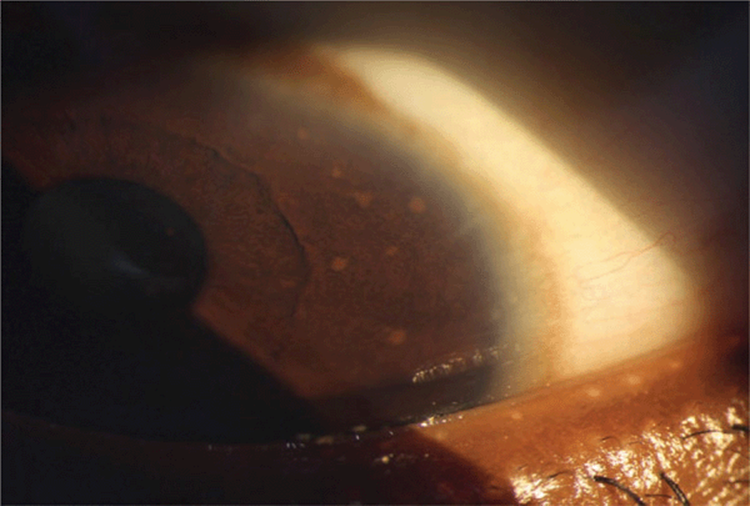

Other Physical Findings. Eyes. Pigmented hamartomas of the iris (Lisch nodules) begin to appear at the age of 5 and are present in 20% of children with NF before age 6 but can be found in 95% of patients with NF1 in adolescence (Fig. 6-10). They do not correlate with the severity of the disease. They are not present in NF2.

Figure 16-10. Lisch nodules are visible only by slit-lamp examination and appear as “glossy” transient dome-shaped yellow to brown papules of up to 2 mm.